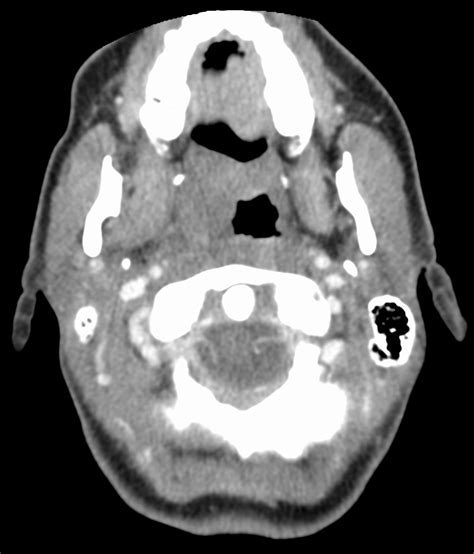

Beyond the numbers, CT FFR interpretation also involves looking at the visual representations generated by the software. These aren’t just pretty pictures, guys; they provide crucial insights into where the flow limitations are occurring. Think of it like a weather map showing areas of high and low pressure. In CT FFR, you’ll often see color-coded maps or 3D models of the coronary arteries. Red, yellow, and blue are common. Generally, red indicates areas of significantly reduced blood flow (low FFR values), yellow might represent moderate reductions, and blue or green often signifies normal or near-normal flow. The goal is to correlate these visual cues with the anatomical findings from the CT angiogram. So, if you see a red area on the FFR map corresponding to a visibly narrowed segment on the original CT scan, that’s a strong indicator that the stenosis is hemodynamically significant. It’s like the map is confirming that the bottleneck you see is indeed causing a real problem downstream. Sometimes, you might see a color change in an area that doesn’t look severely narrowed on the anatomical image. This can happen due to several reasons, and it’s where the sophistication of the computational FFR (cFFR) comes into play. The software analyzes not just the diameter of the stenosis but also factors like the length of the narrowing, the tortuosity (how winding) the artery is, and even the overall pressure gradient across the segment. It’s essentially simulating the physics of blood flow. For instance, a long, smooth narrowing might have less impact than a shorter, more irregular one, even if they look similar in diameter. Interpreting these visual maps requires a careful cross-reference with the primary CT images. You need to be able to identify the specific artery segment corresponding to the colored region on the FFR map. Radiologists and cardiologists are trained to overlay these, mentally or using specialized software, to pinpoint the problematic areas. They’ll look for concordance: does the color map match the anatomical narrowing? If there’s a discrepancy, they’ll investigate further, considering the limitations of the software or potential alternative explanations. Understanding the spatial distribution of the FFR values is just as important as the absolute numbers. Is the reduced flow localized to one specific blockage, or are there multiple areas of concern? This helps in planning the treatment strategy. A single significant FFR lesion might be targeted, whereas multiple mildly reduced FFRs might suggest a more diffuse disease process. These visual aids transform abstract data into a tangible representation of blood flow dynamics within the heart’s arteries, making the interpretation process more intuitive and comprehensive. They are the bridge between the raw data and clinical decision-making.